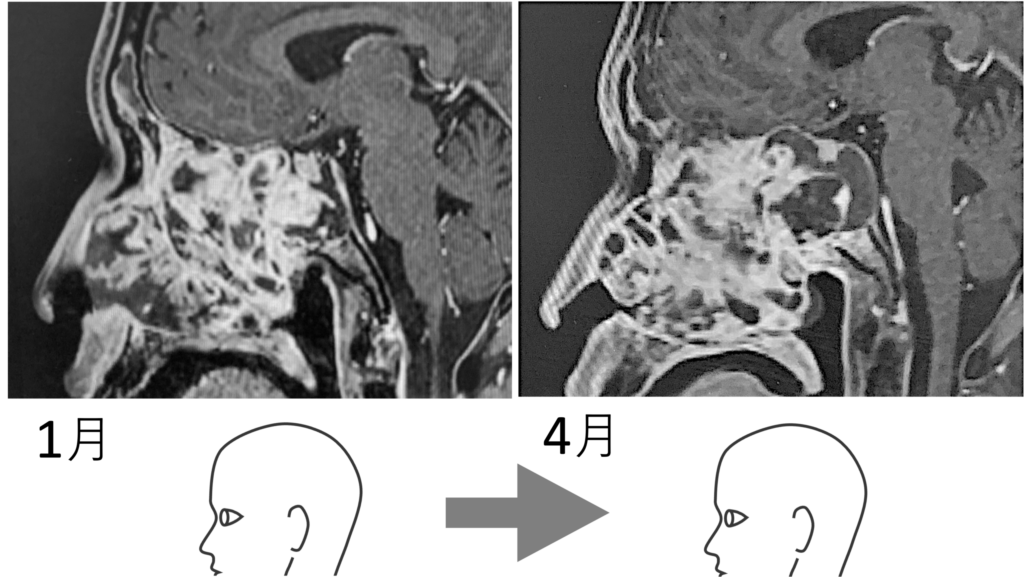

7/17のMRI画像

1月から4月にかけてやや大きくなったかに見えたのは気のせいではなかった。明らかにガンは大きくなっている。その証拠が、耳が聞こえなくなり、左顔面が痺れ、ついで目が見えづらくくなったという現象である。

3月に倒れると宣告を受けた。しかし生きている。すなわち、脳幹 (青で塗りつぶした部分) には近づかず、逆方向の鼻孔や額部に張り出してきていることが画像から分かるのである。ガンがふやけてきた (軟化してきた) から大きくなってきているのであり、大きくなることは必要なのであるが、命の根幹である脳幹を避けるようにして大きくなっているのである。生き続けようとする生命は、こういうことをやってくる。都合のいいように、柔軟にかわしたり変化したりする。決して偶然ではないのである。そういう「印象」を僕は持つのである。それは下リンクのような奇跡を経験してきたからそう思うのである。